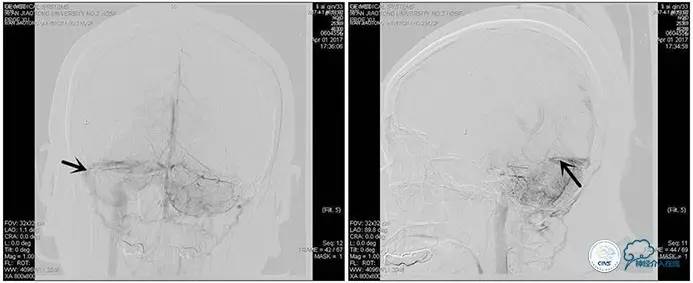

术后造影

术毕远近端压力差为:0